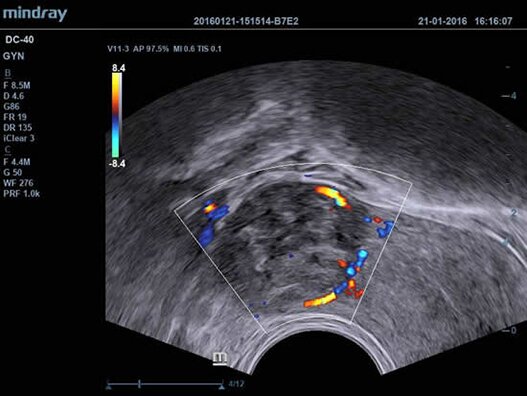

Клинические изображения

- Цветной доплер (Color Doppler);

- V11-3 Микроконвексный внутриполостной датчик для гинекологии, акушерства, урологии